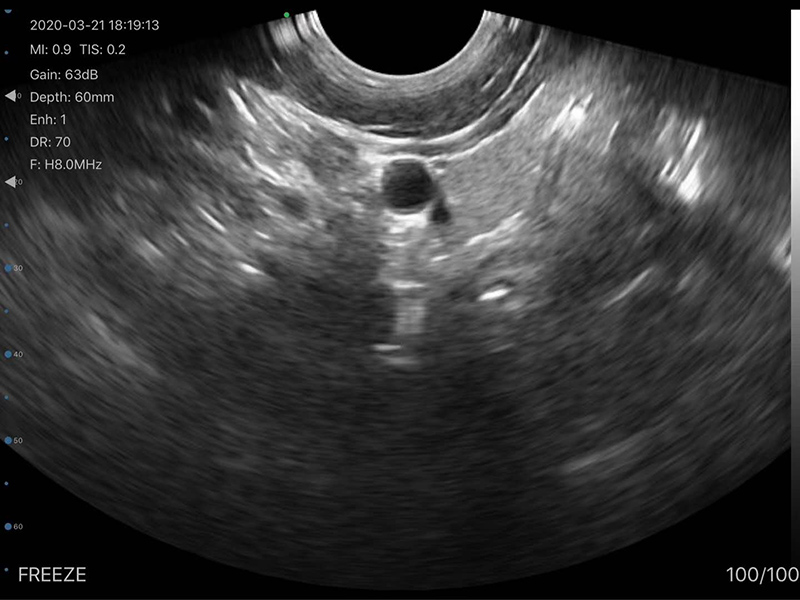

• Probe Head: R60 Convex+R13 Transvaginal

Transvaginal head 6MHz/8MHz, 30/60/90/120mm, R13